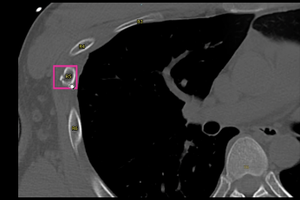

「医療クラウドサービス」は,「SYNAPSE LEAD Cloud」からクラウドサーバーにアップロードされた画像に対し,選択した読影支援機能の解析結果をビューワ上で参照できるサービス。ユーザー登録後,専用ポータルサイトから「胸部X線CADサービス」や「肺結節検出サービス」など,5つの解析機能の中から必要なものを選択するだけで,簡単に利用できる。料金プランは,利用回数に応じた従量課金と,一定期間利用できる定額利用の2種類を用意しており,導入コストを抑えながら,目的や運用に応じた柔軟な活用が可能である。さらに,本格導入前に無料トライアルから利用を開始することもできる。

肺結節検出サービス*7 |

*7 肺結節検出サービスは,肺結節検出プログラム FS-AI688型で実現している。本サービスに含まれる肺結節性状分析機能は画像診断ワークステーション用プログラム FS-V686型,肺区域ラベル機能は画像処理プログラム FS-AI683型で実現している。